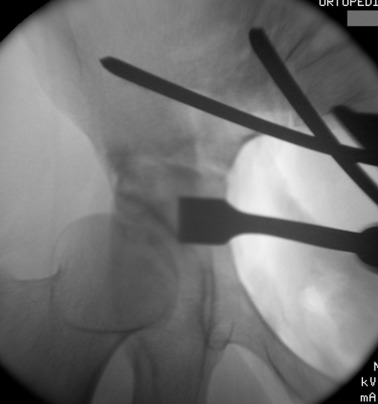

Prior to conducting the osteotomies, the greater sciatic notch, supraacetabular region, pubic rami, and quadrilateral surface were exposed, and the distances were measured as described by Shiramizu et al.15 The first osteotomy was performed on the supra-acetabular region and the iliac wing, from the pectineal line and aiming 1–2 cm distal to the medial of the anterior superior iliac spine (ASIS) (Fig. 4 ). The second osteotomy was performed on the posterior colon of the acetabulum, under fluoroscopic guidance with a 45° oblique view of the iliac. This osteotomy was from the pectineal line to the inferior ischium with an angle of 130° to the first osteotomy, leaving approximately 1 cm of bone posterior to the osteotomy line to preserve the posterior colon, as described in previously conducted anatomical studies (Fig. 5 ).15 The third osteotomy was performed on the pubic arm near to the acetabulum (Fig. 6  ;  Fig. 7 ). And the last osteotomy was performed on the distal ischium, parallel to the inferior acetabular rim (Fig. 8 ). Each stage of the operation was conducted under fluoroscopic control to ensure that the osteotome did not penetrate the joint. By twisting the osteotome under fluoroscopic guidance, it was ensured that the fragment was completely free. After completing the osteotomies, the acetabular fragment was medialized and rotated anterolaterally using a spike-tipped pusher. An anterolateral repositioning of approximately 20° was achieved under fluoroscopy. After the correction, the osteotomy was fixed with 2 or 3 3.5-mm screws (DePuy Synthes, Bettlach, Switzerland), which were inserted percutaneously from the iliac crest to the supraacetabular area, using 0.5- to 1-cm skin incisions.

Ischium osteotomy.

Fig. 8.